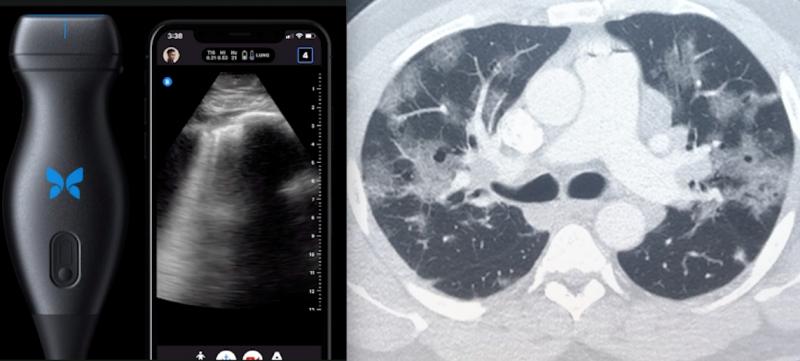

March 21, 2024 — Artificial intelligence can spot COVID-19 in lung ultrasound images much like facial recognition ...